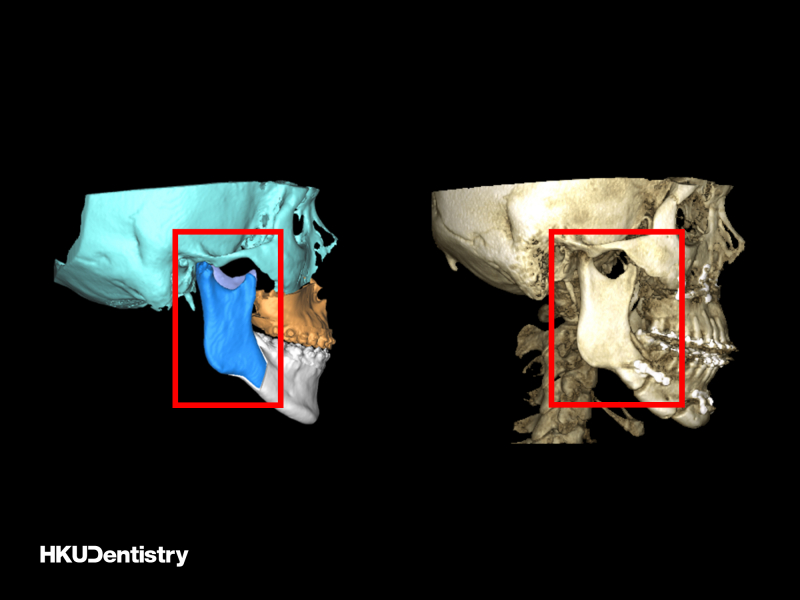

下顎前突症是一種面部畸形,在香港和南中國十分普遍,西方國家相對較少。矯正下顎前突症需要進行正顎手術,手術過程涉及切開顎骨並將它們固定在預先計劃的位置。口內垂直支骨切開術(IVRO)和矢狀支骨切開術(SSRO)是修復過長下顎的兩種常用手術技術。IVRO 是一種較傳統的技術,需要用鐵線固定上下顎 (俗稱鎖口),為期 6 周。在此期間,病人只能進食流質食物。相比之下,SSRO 會使用鈦金屬板和螺絲進行內部固定,手術後即可恢復顎骨功能。這兩項技術在香港和東亞地區都時常採用。